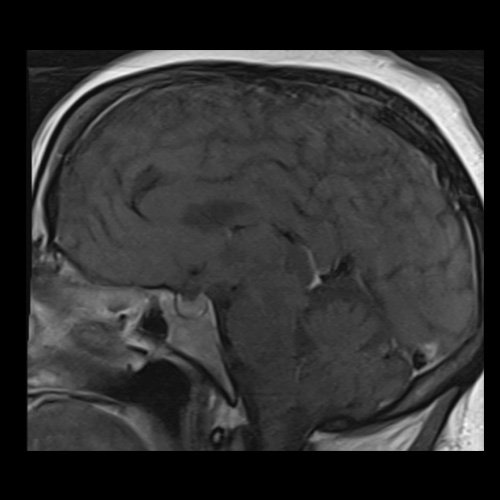

RMN de cráneo con contraste endovenoso (21/02/26) Corte sagital en secuencia T1: sin alteraciones en región selar.

• RMI de cráneo con contraste EV (21/02/26):  Las cavidades ventriculares presentan tamaño y morfología normal. Las estructuras la línea media se hallan en su topografía habitual. A nivel de la fosa posterior el cuarto ventrículo se encuentra en línea media. Bulbo, protuberancia y mesencéfalo sin alteraciones. Relación sustancia gris blanca respetada. No se observan efectos expansivos. El examen de difusión no muestra alteraciones. El efecto FLAIR no muestra alteraciones. La secuencia SWI no muestra alteraciones. No se visualizan alteraciones en proyección, de la región selar, el quiasma óptico y senos cavernosos. No se observan realces patológicos tras la administración de gadolinio.